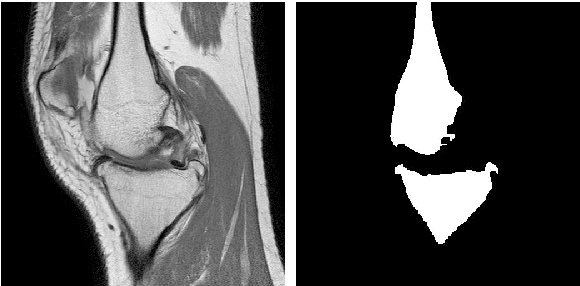

Abstract:Image segmentation is often performed on medical images for identifying diseases in clinical evaluation. Hence it has become one of the major research areas. Conventional image segmentation techniques are unable to provide satisfactory segmentation results for medical images as they contain irregularities. They need to be pre-processed before segmentation. In order to obtain the most suitable method for medical image segmentation, we propose a two stage algorithm. The first stage automatically generates a binary marker image of the region of interest using mathematical morphology. This marker serves as the mask image for the second stage which uses GrabCut on the input image thus resulting in an efficient segmented result. The obtained result can be further refined by user interaction which can be done using the Graphical User Interface (GUI). Experimental results show that the proposed method is accurate and provides satisfactory segmentation results with minimum user interaction on medical as well as natural images.